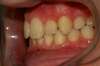

Intra Orale Gauche